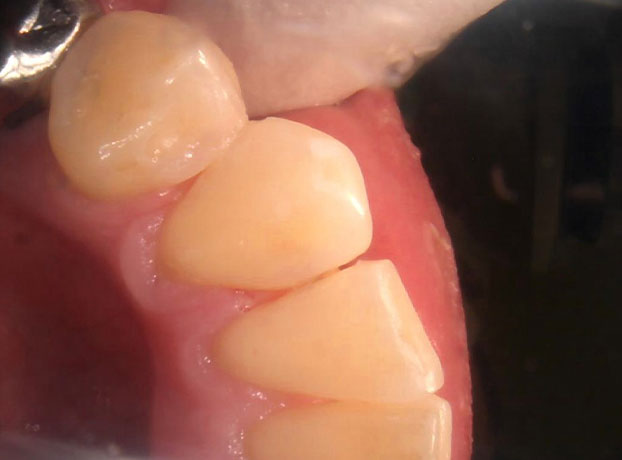

(主訴)痛みはないが虫歯がある

50代男性

前歯の歯と歯の接触部の虫歯を、ピンポイントで虫歯だけ除去して保険治療にてCR(コンポジットレジン)を詰めました。

保険診療で、余分に歯を削らずに虫歯を除去し、治療後見た目も綺麗になりました。